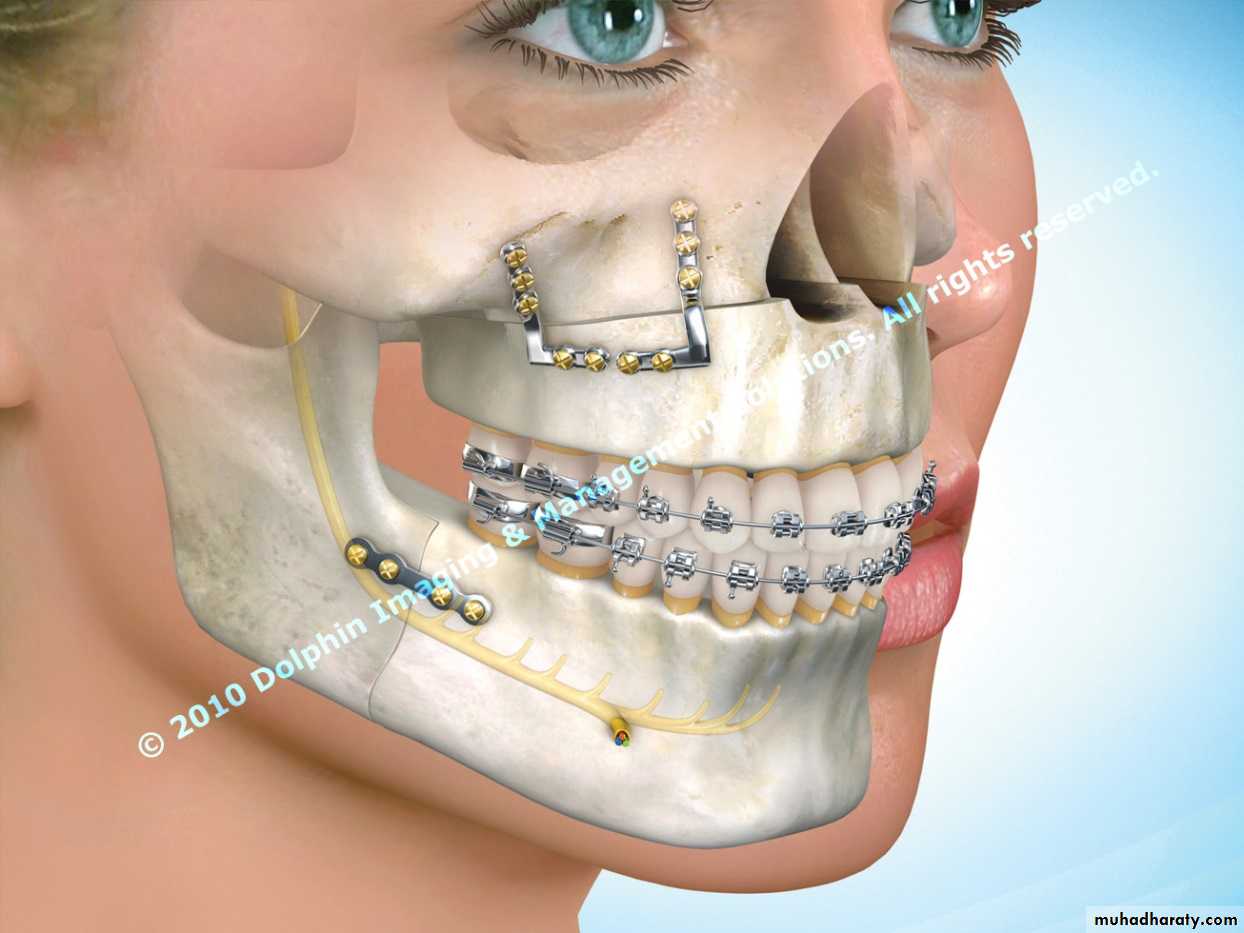

• Three-dimensional computerized tomography (3DCT) is increasingly being used for surgical evaluation and planning .Dental cast

Surgical movement of maxilla and mandible inherently alter the maxillary-mandibular dental occlusion, and as such, careful analysis of the dental models with the orthodontist is essential. The maxillary dental and mandibular dental casts can be studied individually and hand manipulated with each other to assess how the arches are coordinated.Assessment of the models includes space analysis and arch length, transverse width discrepancies, position of the individual tooth within its own arch, and the relationship of the maxillary dentition to the mandibular dentition.

• The surgeon makes osteotomies (ie, incisions) between the teeth in the plaster maxillary cast to create a precise occlusal fit.

• The surgeon then performs the planned surgical procedure on plaster models of the patient’s jaws and teeth and uses these models for reference during the actual surgery.

• The surgeon makes a plastic transitional splint or jig on the model and uses in surgery to position the mandible according to the maxillary position or to position the maxilla based on the position of the mandible

• The jaw may be reshaped on the model until the proper position is obtained.

Good immobilization and fixation is necessary to prevent fibrous union and mal union or non union of the osteotomized segments.